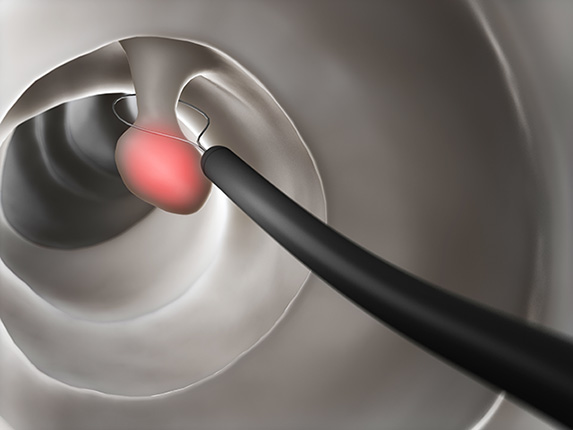

がん化していない病変で小さいものは、大多数が金属性のスネアで物理的に切除するコールドスネアポリペクトミー(CSP)で治療することができます。CSPは消化管に孔が空いたり、後から出血したりといったリスクがほとんどない非常に安全な治療法です。病変が比較的大きかったり、がんも否定できない所見を有したりしている場合などでは、やや侵襲のある通電を併用したホットスネアポリペクトミー(HSP)、粘膜の下に局注を行って病変を筋層から離した上で、スネアで通電して切除する内視鏡的粘膜切除術(EMR)などを行うこととなります。がんが疑われる場合は、病変の形状や大きさなどに応じてHSPやEMR、さらに大きな場合などでは局注を随時追加しながら粘膜を切開・剥離していく内視鏡的粘膜下層剥離術(ESD)といった治療が行われます。内視鏡的切除に関しては、以下もご参照ください。